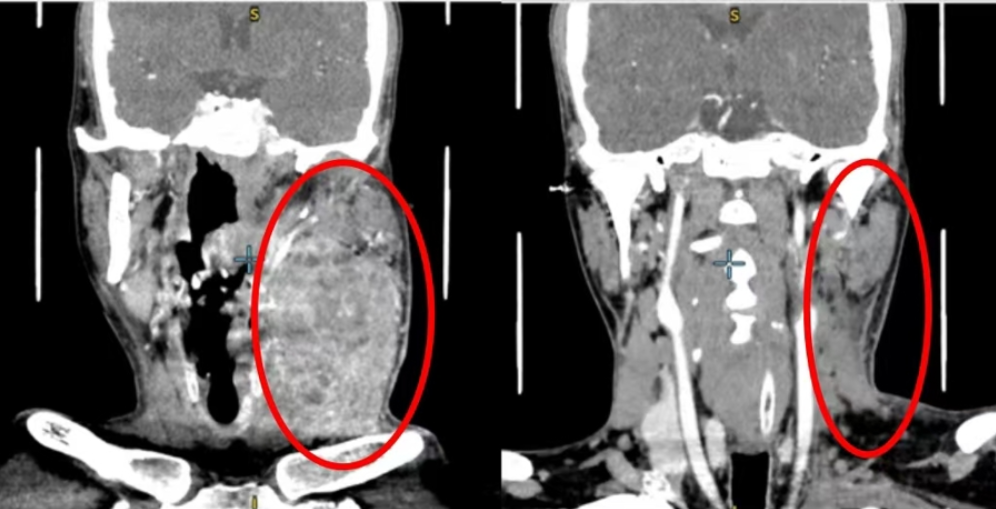

The patient was diagnosed two months ago with advanced squamous cell carcinoma of the tongue (clinical stage T4aN3bM0), a highly aggressive form of oral cancer. By the time of diagnosis, the tumor had already encased the left carotid artery, placing him in a high-risk category where conventional surgery is often considered too dangerous or technically unfeasible.

The results were significant. After standardized treatment, imaging confirmed substantial tumor regression, symptoms improved markedly, and the patient met all criteria for radical surgery — breaking through what had initially been deemed an “inoperable” impasse.